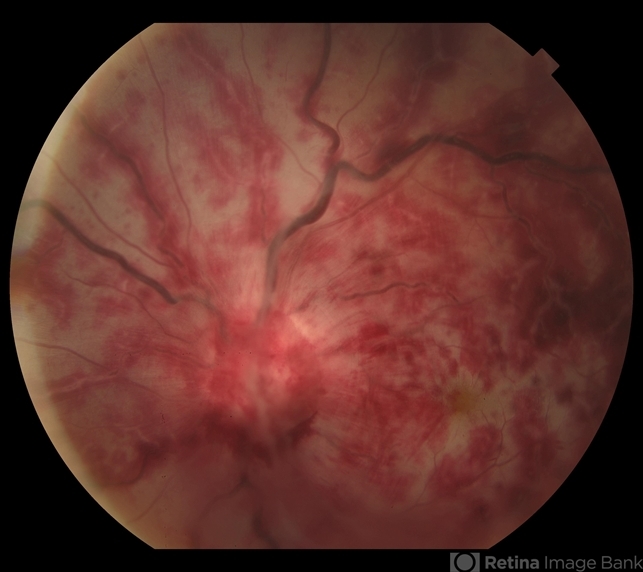

- arterial occlusion, occlusion of retinal vein

- 32-year-old female with a sudden loss of vision in the left eye. This fundus photograph shows central arterial occlusion plus central vein occlusion secondary to ophthalmic artery occlusion. This patient has thromboangitis obliterans.